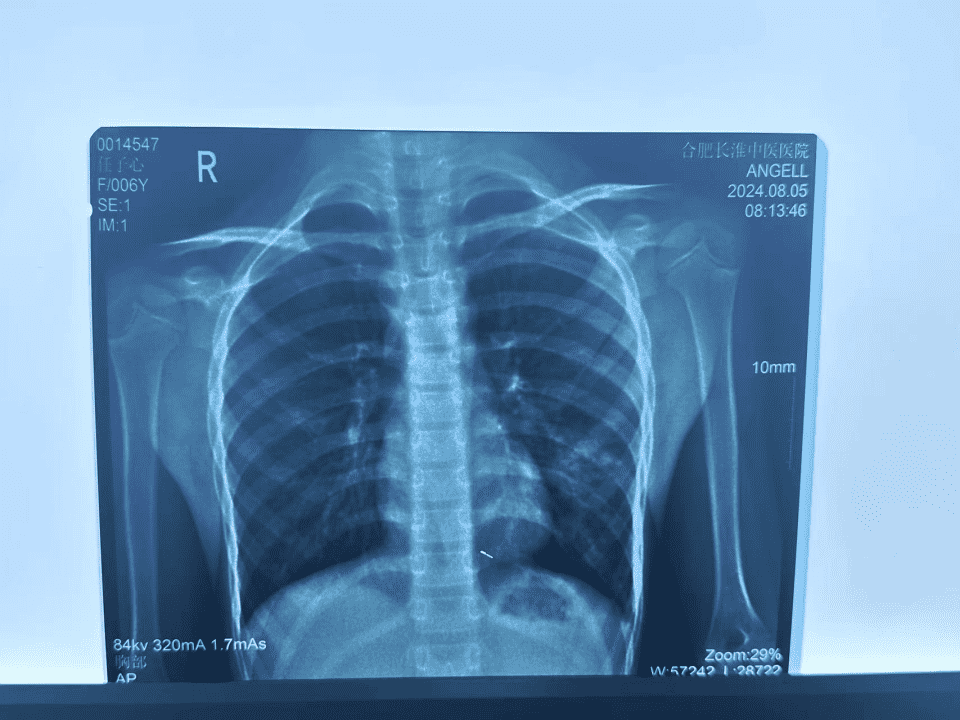

6岁小女孩高烧难退,家人焦急寻医

来自合肥市瑶海区6岁的小女孩,1周前因受凉后恶寒、发热,最高腋温39℃,于当地诊所治疗,症状未见缓解。2天后出现咳嗽、痰粘难咳出,在当地某院住院治疗,症状未见明显好转。出院后自行服药,腋温仍有38.7℃。家人心急如焚,经熟人介绍就诊于我院,呼吸专家诊断,拟“大叶性肺炎”住院治疗。

(患者CT报告)

6岁的小患者高烧难退,伴有咳嗽、咳痰,经我院肺病科专家治疗,高烧已退,咳嗽也有所缓解,心肌酶指标已下降。李教授同意我院肺病科专家的治疗方案,对采用保护心脏、抗氧化反应的药物给予了肯定。新冠疫情期间,李教授担任合肥市新冠肺炎医疗救治和病例诊断专家组组长,她指出,目前常见的病毒感染有两种:新冠和甲流。她根据数十年丰富的临床经验和专业成就,详细分析了病毒感染和细菌感染的区别。根据小患者的病情和各项检查,她应该是属于细菌感染(肺炎链球菌感染),儿童正处于生长发育阶段,肝肾功能尚未完善,在用药上需采用儿童剂型,如抗菌药希刻劳(通用名:头孢克洛干混悬剂)。